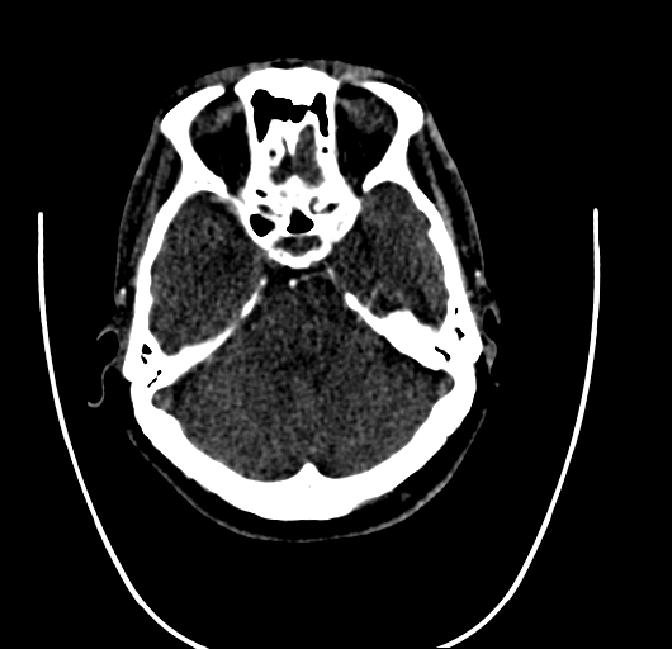

Figure 4.3: Segmentation on internal carotid arteries. Unaltered image (left). No pretrain model (mid-left). Fine-tuned model (mid-right). Hand-labeled ground truth (right).